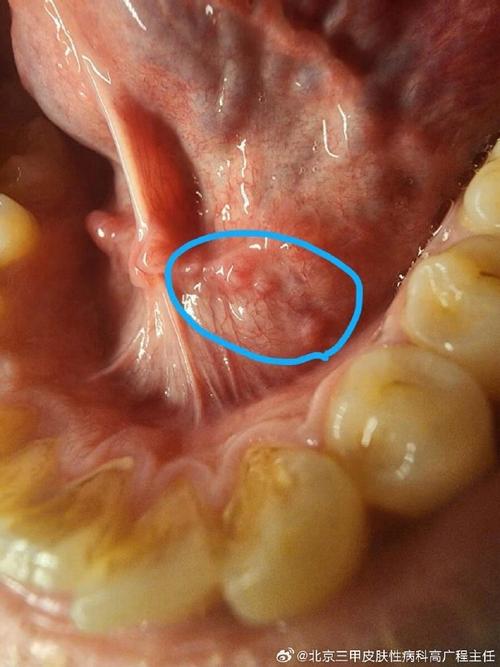

口腔上长硬疙瘩是啥原因?

下面我为您分析一下口腔上颚长硬疙瘩的几种常见可能性,您可以根据自己的情况进行初步判断,但最终还是要以医生的诊断为准。

口腔癌(如鳞状细胞癌)

这是最需要警惕,但相对少见的情况。

- 外观:

- 通常表现为长期不愈合的溃疡(超过两周)。

- 肿块质地坚硬,像骨头一样,且固定不动(与周围组织粘连)。

- 表面可能凹凸不平、呈菜花状。

- 早期可能没有疼痛感,但后期可能出现疼痛、麻木、出血、张口受限等症状。

- 高危因素:长期吸烟、酗酒、咀嚼槟榔、HPV病毒感染等。